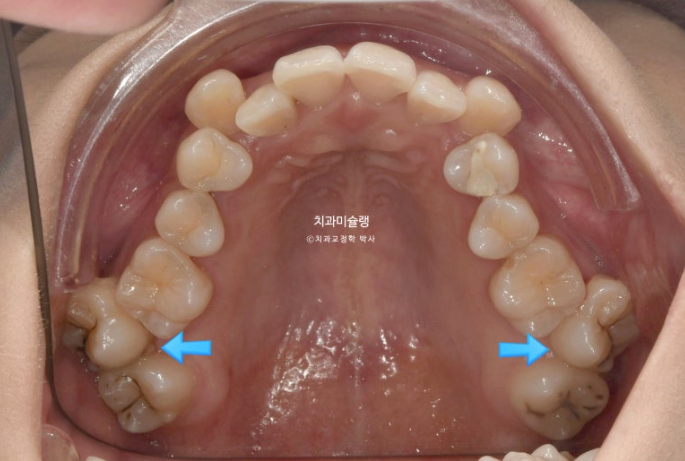

23.08

파란화살표는 가위교합입니다.

통상 비발치 덧니 교정은 사랑니를 빼고 사랑니 공간을 이용하여 덧니 펼 공간을 만드는 것을 목표로 합니다.

하지만 이 경우 맨 뒤 사랑니를 빼지 않고 파란 화살표 제2대구치를 발치했습니다. 발치한 제 2대구치 자리에는 사랑니로 대체해서 교정을 마무리 하는 방법입니다.

사랑니 대신 제 2대구치를 빼는 이유는 가위교합의 원인 치아를 제거하고 구치부 후방이동을 수월하게 하는 장점을 얻기 위해서이며 이 분은 맨뒤 사랑니가 두번째 큰어금니와 모양 사이즈가 동일했기 때문에 가능한 치료방법입니다.

즉 사랑니가 제 2대구치를 기능적으로 충분히 대체할 수 있는 상황

제 2대구치 발치교정 케이스는 좀 더 포스팅 해보도록 하겠습니다. 제2대구치가 많이 썩어있는 경우 사랑니 대신 제2대구치를 발치하고 아직 나오지 않은 fresh한 사랑니를 제2대구치 자리로 끌어오는 치료를 합니다.

인비절라인 치료를 선택하셨고 아래 매복사랑니 1개를 빼고 위에는 사랑니 대신 양쪽 제 2대구치를 빼고 치료에 들어갑니다.